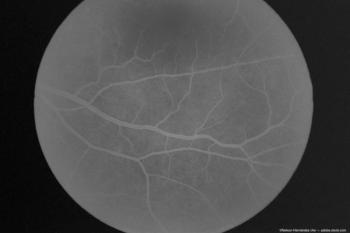

They went on to explain that biomarkers such as VD in the superior capillary plexus (SCP), deep capillary plexus (DCP), and foveal avascular zone (FAZ) are promising because previous studies have reported changes in vascular density in the brain and retina in AD.

Sruthi Arepalli, MD, spoke with Modern Retina about her presentation, "Assessing retinal vascular changes in alzheimer disease with radiomics: A preliminary study of fundus photography" at the annual ASRS meeting in Stockholm, Sweden.